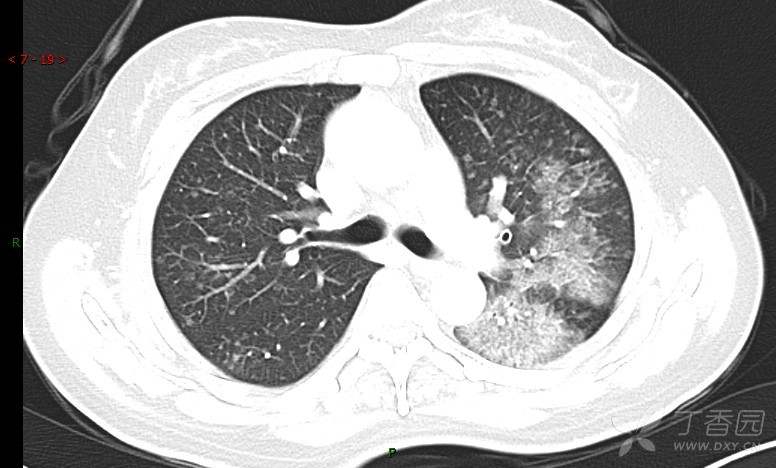

腺泡结节影,蜂窝征,这些都在提示……(病例3连发,附其他2例链接,病理已公布)

咳嗽1年余,加重7天。

患者于1年余前始受凉后出现咳嗽,多为干咳,未在意,未到医院就诊。近3月患者出现咳痰,多为黄色粘痰,量大,伴乏力,偶有头晕、心慌,无发热、胸痛、憋喘,无低热、盗汗、咯血、胸痛,无头痛,无恶心、呕吐、腹痛、腹泻,无尿频、尿急、尿痛,在当地诊所给予抗感染等对症支持治疗(具体药物及剂量不详),症状仍时有反复。患者于1月余前到外院就诊,行胸部CT提示双肺炎症,左肺重,考虑为“间质性肺炎”,给予“左氧氟沙星、利巴韦林、头孢哌酮舒巴坦钠注射液”治疗,复查胸部CT示病灶吸收不理想,后出院继续于诊所对症治疗(具体药物及剂量不详),效果欠佳。7天前患者无明显诱因出现上述症状加重,为求进一步诊治,特来我院就诊,我院门诊以“肺炎(重症)?”收入留观室,留观室给予“盐酸莫西沙星氯化钠”等对症治疗后,今日转入我科。患者自发病以来,神志清,精神差,饮食正常,睡眠增多,大小便正常,体重近3月减轻5公斤余。